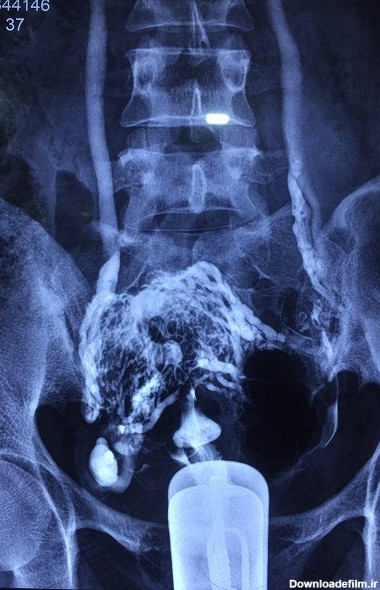

کرج کجا برای عکس رنگی رحم با بیهوشی برم سونوهیستروگرافی و هیستروگرافی یا عکس رنگی رحم یا (HSG) با بی حسی یا بیهوشی ، بدون درد و بدون خونریزی ، با کتتر مخصوصدر

الزاما در عکسبرداری رنگی رحم فرد بیهوش نمیشود، بنا به صلاحدید پزشک و انتخاب بیمار تصمیمگیری میشود که آیا بیمار تحت بیهوشی قرار گیرد یا خیر؟

عکس رنگی رحم در کلینیک رادیولوژی مرکز درمان ناباروری ابنسینا، هم با بیحسی هم و هم با بیهوشی انجام میشود.تمام پرسنل این کلینیک خانم، و همگی بسیار مجرباند و نتیجه عکس بلافاصله پس از انجام آن توسط متخصص محترم رادیولوژی به مراجعان محترم داده میشود.شماره تماس برای دریافت نوبت: ۰۲۱-۲۳۵۱۹